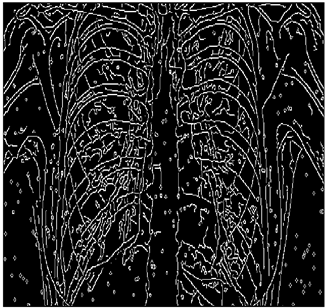

Table 13. Edge-detected image of “X-ray 4” after binarization for different noises.

NoiseCannyStandardSmooth

No noise Mathematics 10 02421 i135 Mathematics 10 02421 i136 Mathematics 10 02421 i137

G(0.001) Mathematics 10 02421 i138 Mathematics 10 02421 i139 Mathematics 10 02421 i140

G(0.002) Mathematics 10 02421 i141 Mathematics 10 02421 i142 Mathematics 10 02421 i143

G(0.003) Mathematics 10 02421 i144 Mathematics 10 02421 i145 Mathematics 10 02421 i146

I(0.25%) Mathematics 10 02421 i147 Mathematics 10 02421 i148 Mathematics 10 02421 i149

I(0.5%) Mathematics 10 02421 i150 Mathematics 10 02421 i151 Mathematics 10 02421 i152

I(1%) Mathematics 10 02421 i153 Mathematics 10 02421 i154 Mathematics 10 02421 i155

For Table 11, Table 12 and Table 13, the same points of Table 10 can be made. Therefore, for the sake of brevity, the points are not mentioned.